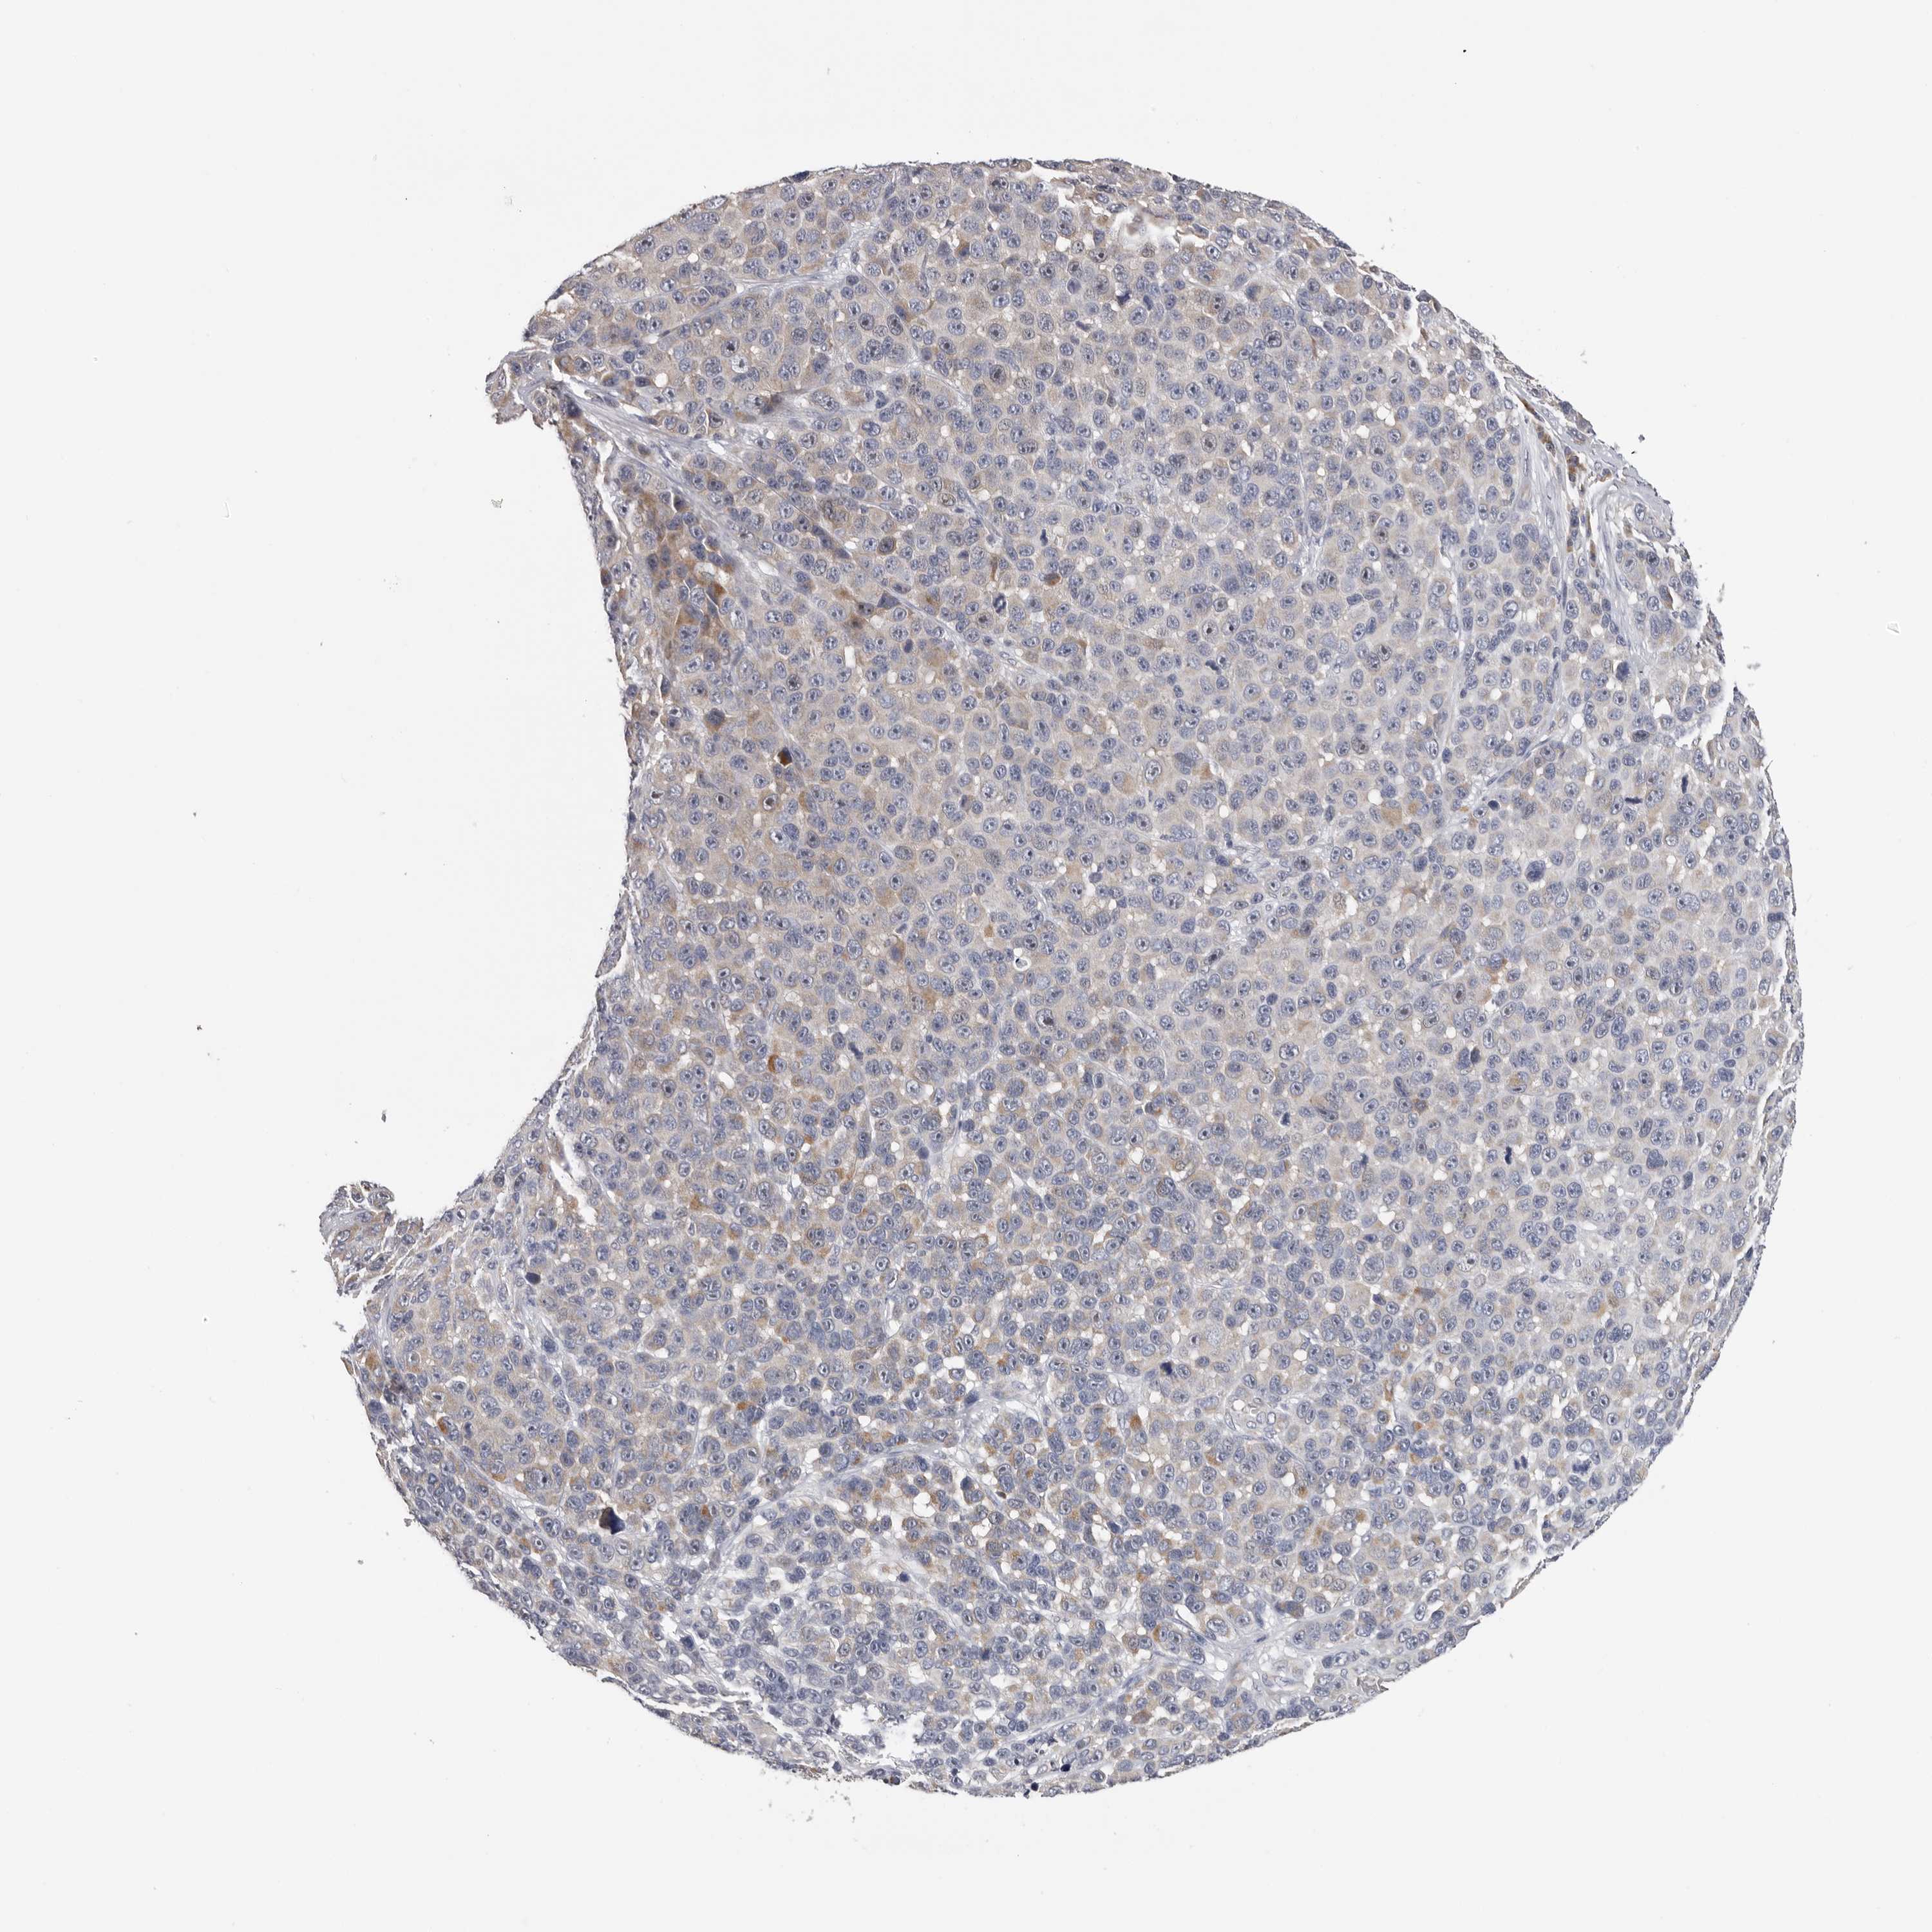

MELANOMA - Protein expressioni

A mouse-over function shows sample information and annotation data. Click on an image to view it in a full screen mode. Samples can be filtered based on level of antibody staining by selecting one or several of the following categories: high, medium, low and not detected. The assay and annotation is described here.

Note that samples used for immunohistochemistry by the Human Protein Atlas do not correspond to samples in the TCGA dataset.

Antibody stainingi

Antibody staining in the annotated cell types in the current human tissue is reported as not detected, low, medium, or high, based on conventional immunohistochemistry profiling in selected tissues. This score is based on the combination of the staining intensity and fraction of stained cells.

Each image is clickable and will lead to virtual microscopy that enables deeper exploration of all samples and also displays staining intensity scores, fraction scores and subcellular localization as well as patient and tissue information for each sample.

Antibody HPA023081

Antibody HPA023103

Antibody HPA024795

Staining

High

Medium

Low

Not detected

Intensity

Strong

Moderate

Weak

Negative

Quantity

>75%

75%-25%

<25%

None

Location

Nuclear

Cytoplasmic/membranous

Cytoplasmic/membranous,nuclear

Malignant melanoma, NOS

Malignant melanoma, Metastatic site